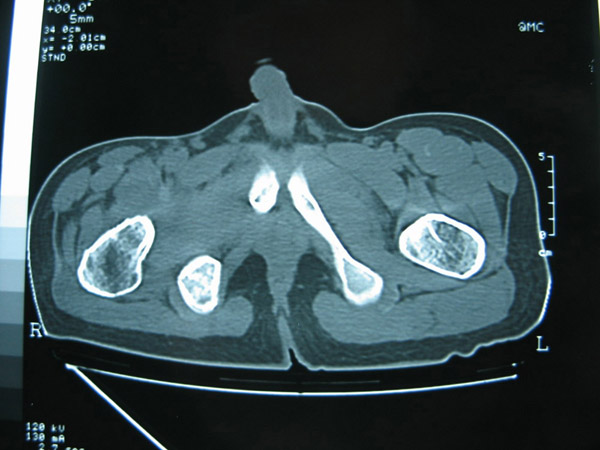

以下是引用hhcckk在2007-1-25 17:18:00的发言:[br][br]支持髋关节结核,[br]依据关节面破坏,有脓肿,脓腔内有钙化,关节周围增生不明显,鉴别[br]1化脓性的病变增生明显,临床上有高热[br]2创伤引起的关节炎,无菌坏死不会引起关节面的破坏,而且不会在这么短的时间内出现[br]

以下是引用卜一在2007-1-25 16:33:00的发言:[br]右侧髋关节股骨头及髋臼骨骨小梁疏松 粗糟,股骨头外形毛糟,软组织似肿胀,间隙略变窄.考虑:1 髋关节结核可能性大.2 缺血性坏死?3 化脓性髋关节炎?